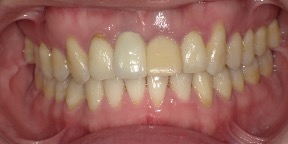

29歳女性のビフォーアフター

| 診断 | 叢生(デコボコがある状態)、過蓋咬合 |

| 治療方針 | インビザラインシステムにて主にIPR(歯と歯の間をわずかに削合してスペースを獲得する方法)を組み込んだ動的矯正治療を行い、叢生を改善後、保定を行う。臼歯部の咬合関係はプランの関係上維持して叢生と前歯部の咬合改善を目指した。 |

| 治療費 ※ | 60万4千円(診断、型取り、PMTC、保定装置を含む料金) |

| 治療期間 | 1年5か月 |

| リスク | 1日20時間以上マウスピースを使用できない場合、歯が動かない可能性がある。装着時や食事時に痛みを伴う。歯肉退縮や虫歯になるおそれがある。また、指導通りに装着できていない場合や適切なブラッシングが出来ていないとそのリスクが高くなる。歯根が短くなることがある。ごくまれに歯の神経が損傷してしまうことがある。過去にぶつけたり深い虫歯治療をしたことがあるとそのリスクはやや高くなる。矯正後には保定装置が必要。適切な使用ができない場合、後戻りの原因となる。将来的に歯並びが動いて再矯正が必要な場合がある。親知らずが正常に生えていない場合、その可能性がやや高くなる。 |